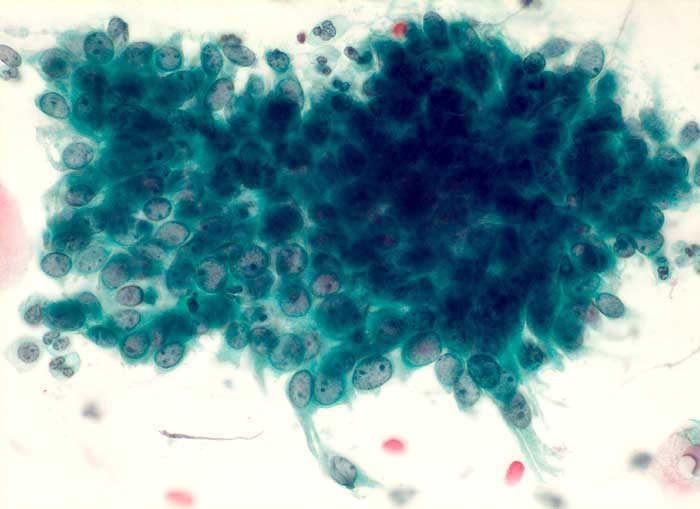

regeneratorische Veränderungen des Zylinderepithels

Portioabstrich: Zylinderepithelien mit vergrösserten Kernen und hoher Kern-Plasma Relation. Grosse Nukleolen. Vesikuläre Kerne mit feinem Chromatin und regelmässiger Kernmembran. Die Zellen sind in regelmässigen Abständen voneinander gelagert.

Die DNA-Hybridisierung zum Nachweis von HPV-Sequenzen ergab:

HPV Typ low grade (6/11/42/43/44) negativ. HPV Typ high grade (16/18/31/33/35/45/51/52/56) negativ.